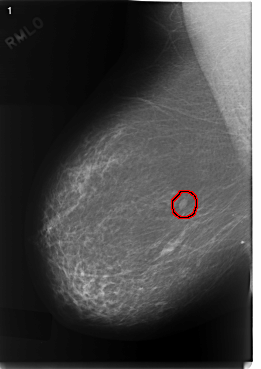

C_0331_1.RIGHT_MLO

FILE: C_0331_1.RIGHT_MLO.OVERLAY

TOTAL_ABNORMALITIES 1

ABNORMALITY 1

LESION_TYPE MASS SHAPE OVAL MARGINS CIRCUMSCRIBED

ASSESSMENT 3

SUBTLETY 5

PATHOLOGY BENIGN

TOTAL_OUTLINES 1

BOUNDARY